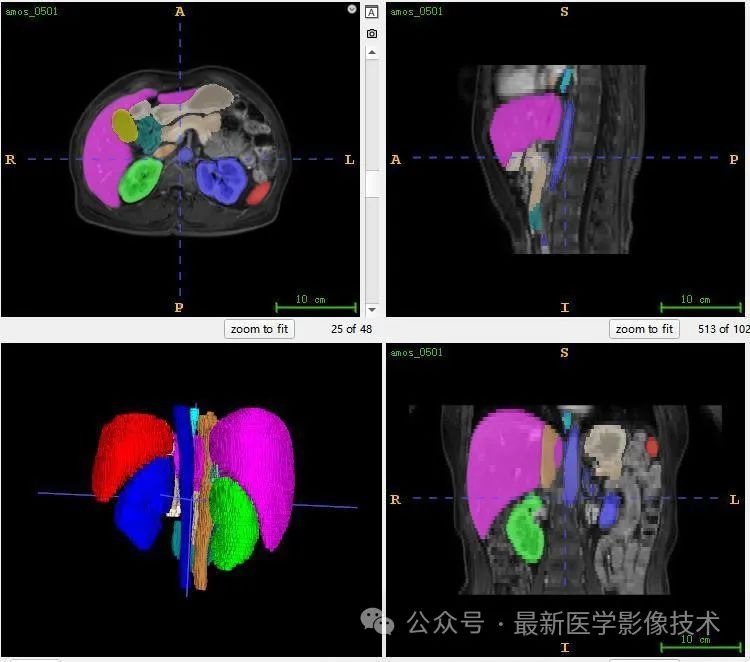

12、验证集分割结果

左图是金标准结果,右图是预测结果。

13、测试集分割结果